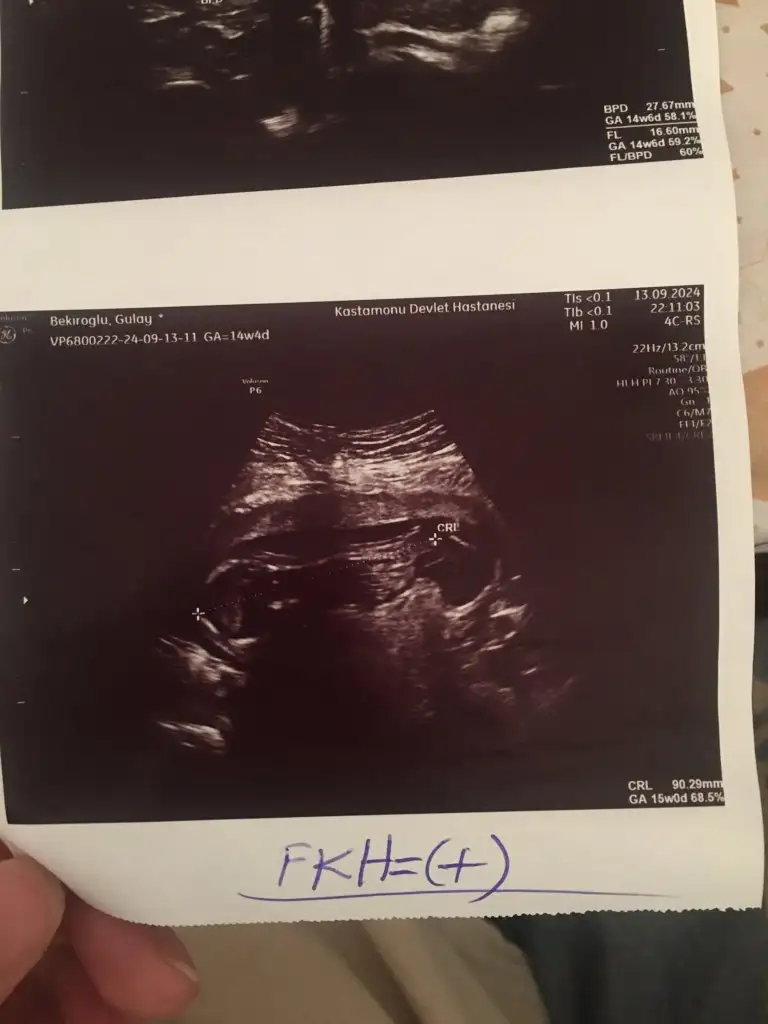

İçimden kız geçti annesi. Çok anlaşılmıyor. Ama ilk kese fotoğrafları i atarsan onlar da ipucu oluyor. Ayrıca neden grupta yoksunuz şubat annesi :anneadayı: :KK200::KK200:

Benim bebişime de bakar mısınız 20 haftalık olacak neredeyse ama önce erkek sonra kıza döndü